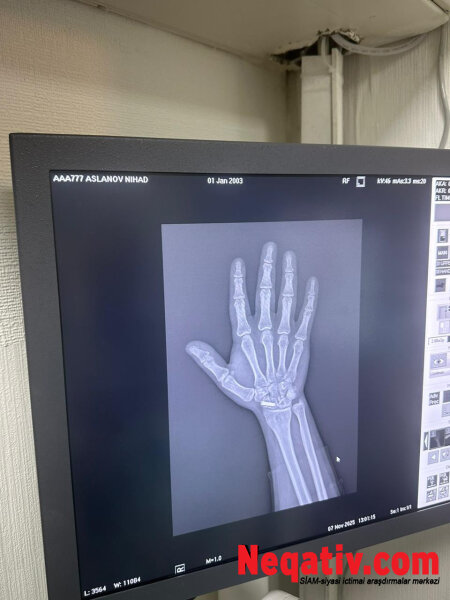

N.Aslanovun sözlərinə görə, universiteti bitirdikdən sonra Səfərbərlik Xidmətinin Rayon Şöbəsinə müraciət edib və könüllü xidmət etmək istəyini bildirib. Lakin 2022-ci ildə keçirdiyi ağır əməliyyat nəticəsində sağ biləyinə yerləşdirilən daimi mil ciddi problem yaradıb.

“Nizami Tibb Mərkəzi, Travmatologiya İnstitutu və hərbi komissarlığın (Red- Səfərbərlik Xidmətinin) öz həkimləri qolumdakı milə və funksiya pozuntusuna görə məni hərbi xidmətə yararsız hesab ediblər. Əməliyyat edən həkimim Zahid Cəfərovun diaqnozuna görə, mən 5 kiloqramdan artıq yük qaldıra bilmərəm, soyuq havada qolum sızıldayır və barmaqlarımın hərəkəti məhduddur. Əlim silah tutacaq vəziyyətdə deyil”,-deyə çağırışı Nihat Aslanlı bildirib.

“6 ay sonra yenidən yoxlanışa çağırdılar. Bu dəfə Səfərbərlik Xidməti mənə bildirdi ki, biz səni yararsız yazsaq da, Sosial Müdafiə Fondu bizim rəyimizin üstündən xətt çəkərək səni yararlı hesab edib. Səbəb kimi isə göstərirlər ki, guya mənə o 6 ayı qolumdakı mili çıxartdırmaq üçün veriblər. Hansı ki, o mil ömürlükdür və sümük hələ də bitişməyib. Mili çıxartmaq əlimin tamamilə iflic olması deməkdir”.